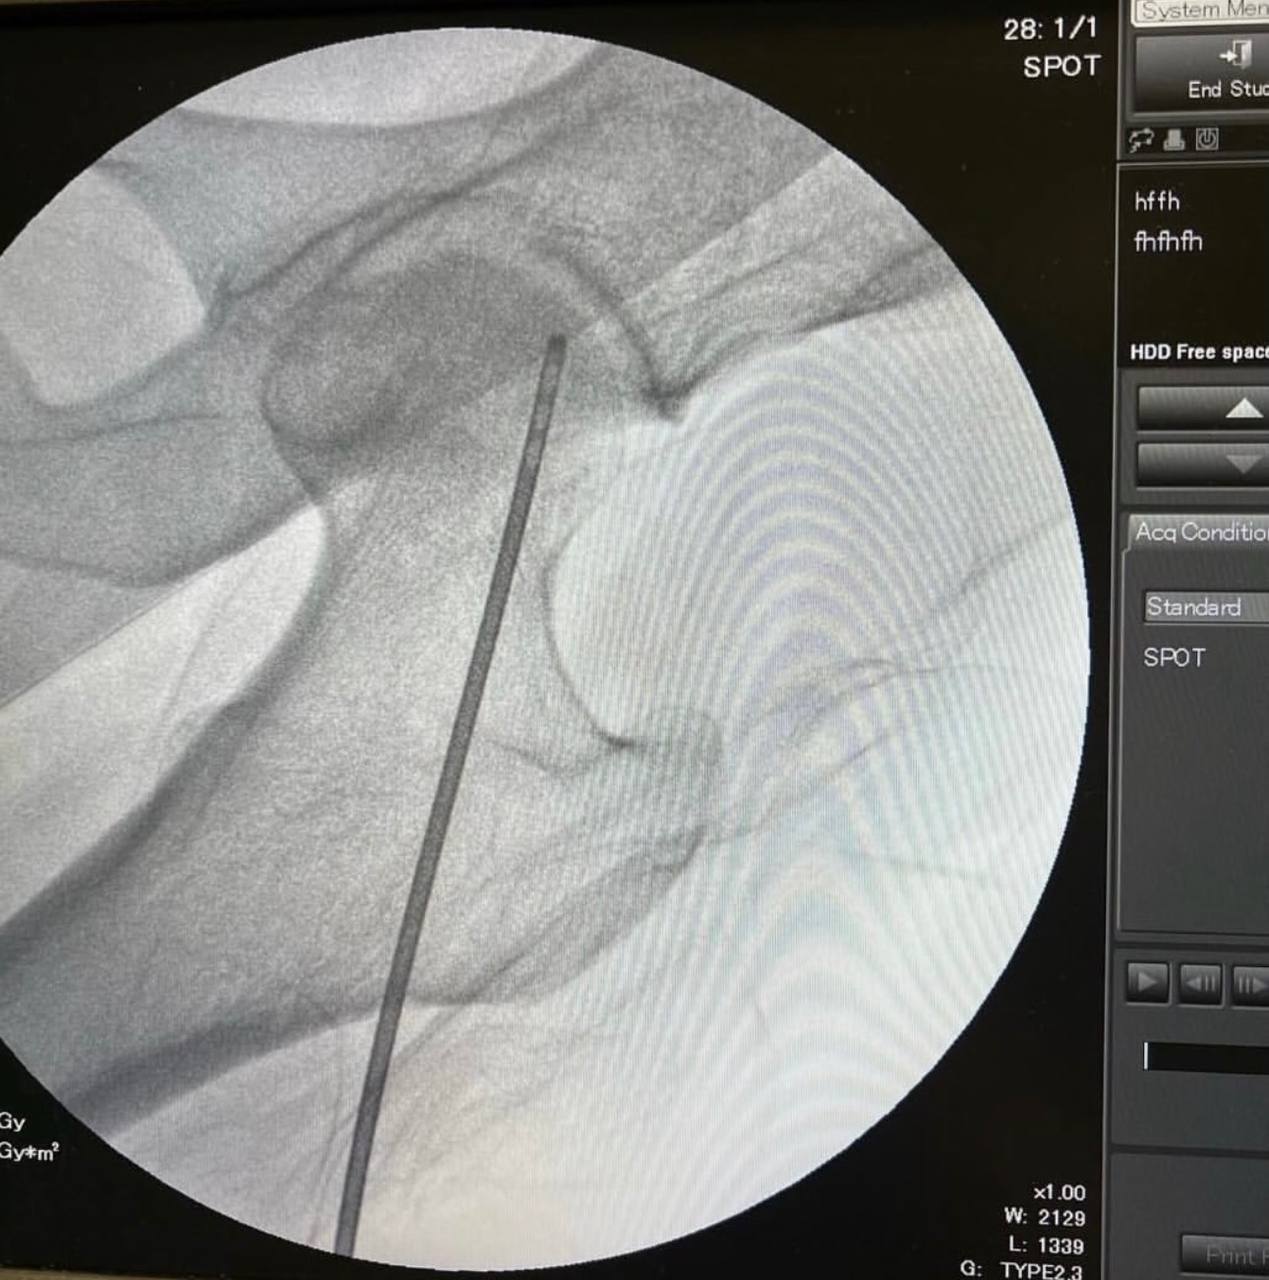

Заведующий отделением травматологии №1 Гамиль Гарифуллов предложил методику, которая дает возможность отсрочить замену суставов. Травматологи просверлили канал до очага некроза и ввели в него стволовые клетки. Перед операцией травматологи забирают жировую ткань с передней брюшной стенки, центрифугируют и поучают стромально-васкулярные клетки. Смешивают их с плазмой пациента и этот «коктейль» вводят в очаг некроза.